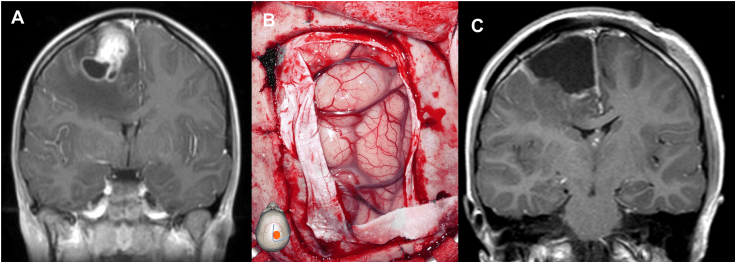

enfant de 9 ans, ATRT précentrale révélée par HTIC ; survie sans récidive à 10 ans de la résection suivie de radio-chimiothérapie - une tumeur de la fosse postérieure (surtout angle ponto-cérébelleux avec hydrocéphalie